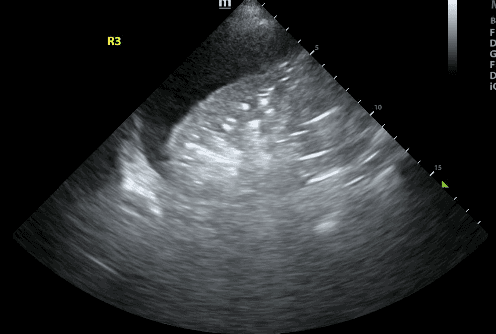

Lung ultrasound has revolutionized respiratory assessments in modern medicine, offering real-time, non-invasive, and radiation-free insights into lung conditions. It uses sound waves to create images that reflect lung pathology and its simplicity, portability and rapid applicability make it an indispensable tool for clinicians. These features also make it highly effective in reducing the need for bedside chest X-rays and CT scans.

Although ultrasound had been integrated into almost every medical specialty by the 1990s, it had never been used to evaluate the lung. This was primarily because air in lung scatters ultrasound waves, resulting in artifacts that can be difficult to interpret. However, in the late 1990s, Daniel Lichtenstein, who is often referred to as the “father of lung ultrasound,” published a landmark paper describing the interpretation of lung ultrasound artifacts to detect lung pathology.

Lichtenstein’s work dramatically transformed the diagnostic and therapeutic landscape of lung ultrasound. Continued innovation and research demonstrated that artifacts called B lines correlated with thickening in the spaces between lung units - a condition now known as “interstitial syndrome.” Furthermore, Lichtenstein recognized that airless (ie. consolidated) lungs could be easily visualized with lung ultrasound.

While initially used by intensivists to assess critically ill patients, lung POCUS is now used in almost every specialty - from Trauma teams who use it to rapidly diagnose pneumothorax, hemothorax and lung contusions to Radiologists and Internists who use it to identify safe needle insertion sites for drainage of pleural effusions. In the Emergency Department and Intensive care unit, lung POCUS has been shown to expedite diagnosis and reduce the number of imaging studies.